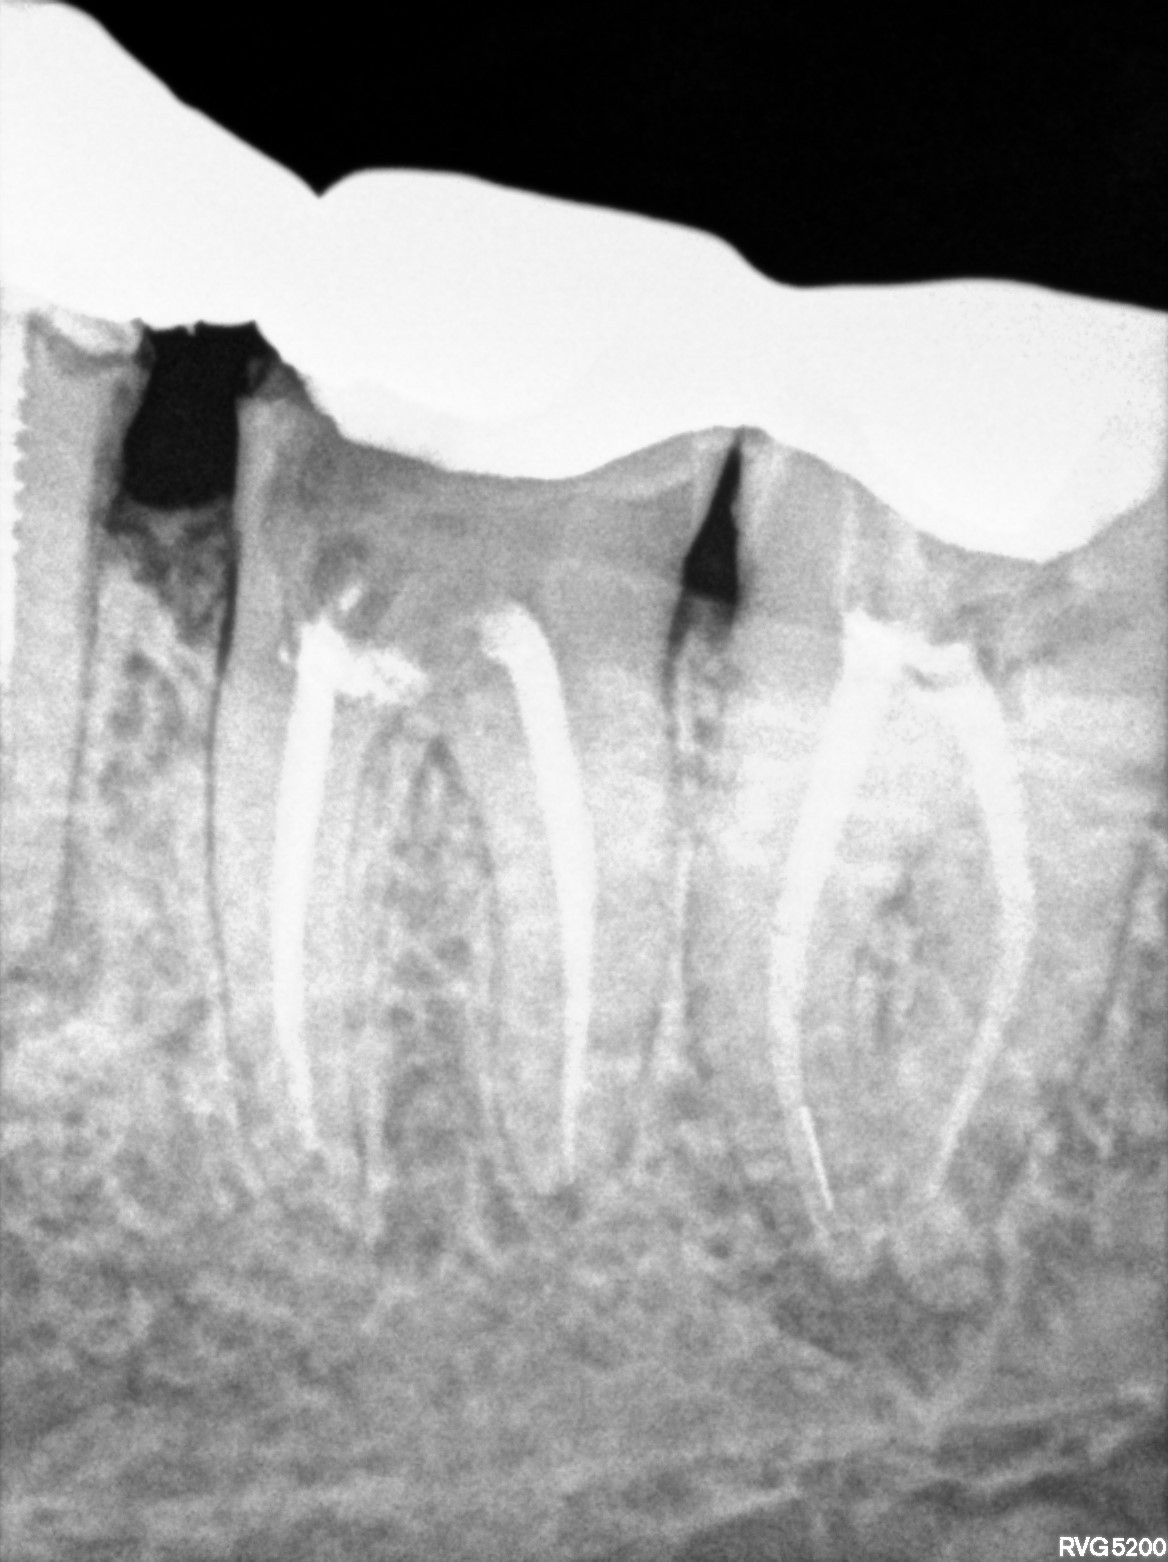

Dental Radiographs FHIR: DocumentReference · LOINC 24641-7

R55.jpg

24641-7